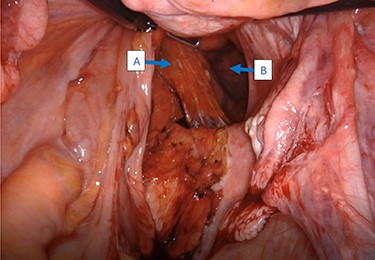

A 62-year-old post-menopausal female presented with worsening fecal urgency, incontinence and a corresponding perianal bulge that was increasing in size over the past 2 years. The patient had a recent history of significant weight loss through diet modification. Medical history was significant for two previous vaginal deliveries, 15-pack per year smoking history, hypothyroidism, hiatal hernia, previous CVA and chronic obstructive pulmonary disease. Fifteen years prior, the patient underwent a total vaginal hysterectomy, including a McCall culdoplasty, anterior and posterior repairs, sacrospinous ligament suspension and tension-free vaginal taping to treat symptomatic cystocele, rectocele and descent of the uterus. A previous computed tomography (CT) demonstrated a heterogeneously enhancing mass extending from the right posterolateral margin of the lower vaginal cuff and perirectal region into the ischioanal fossa, suggestive of, but not definite for a soft tissue mass (Fig. 1). Upon clinical exam, the patient was noted to have a defect in the right levator muscles complex with complete herniation of her rectum through this defect. This hernia created pocking of the stool and difficulties with stool emptying. In addition, the patient had to adjust her sitting position to avoid unwanted stool leakage as a result of spontaneous hernia reduction. The patient was offered an abdominoperineal resection; however, discussion of laparoscopic interventions with the DaVinci robot quickly became the best option for repair. Informed consent was obtained for robotic repair, and routine preoperative colonoscopy was performed.

Intraoperatively, cystoscopy and intraurethral ICG injection were performed as a routine practice to aid with the identification and protection of ureters in redo pelvic surgeries. The abdomen was accessed using the Veress needle technique, and robotic trocars were placed in transverse fashion at the level of the umbilicus. Initially, a medial-to-lateral mobilization of the descending colon was performed. The mesorectal fascial plan was entered posteriorly and the rectum was circumferentially mobilized. The pelvic defect was encountered on the right side, and it was noted that the rectum was redundant, folded on itself and contained by the hernia sac (Fig. 2). Using meticulous dissection, it was reduced completely. The hernia roof consisted of the gluteal skin only. The hernia neck was wide and consisted of defects in the levator muscle. The anal canal formed part of the hernia wall.

Intraoperative view of the rectum (A) herniating through a defect in the pelvic wall (B).